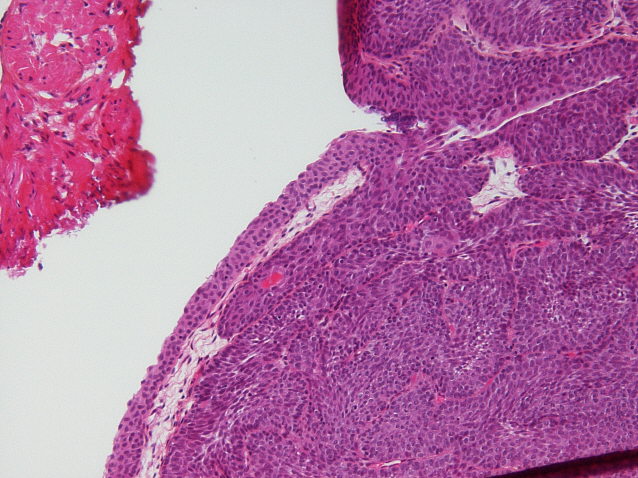

Bladder Papillary Lesions

Case ID: 464